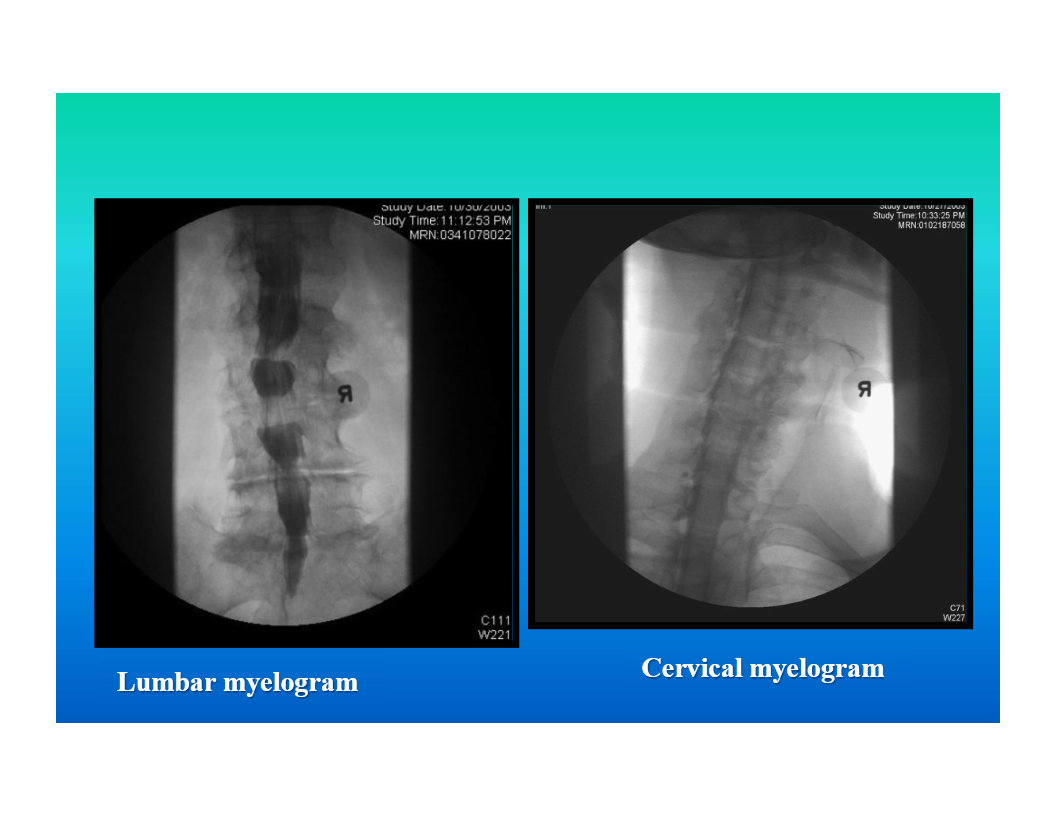

myelography

introduction of contrast material into the spinal subarachnoid space

used to evaluate disc disease as well as diseases in and around the spinal cord